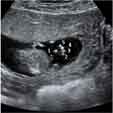

Las ecografías permiten distinguir el sexo del feto. En este ultrasonido en 3D, el bebé de 11 semanas de gestación se cree que es una niña, aunque no se puede asegurar todavía. Los genitales externos se empiezan a formar en la semana 8 de embarazo y terminan hacia la semana 12.

El tubérculo genital (flecha) apunta hacia abajo, lo que hace muy probable que se trate de una mujer.